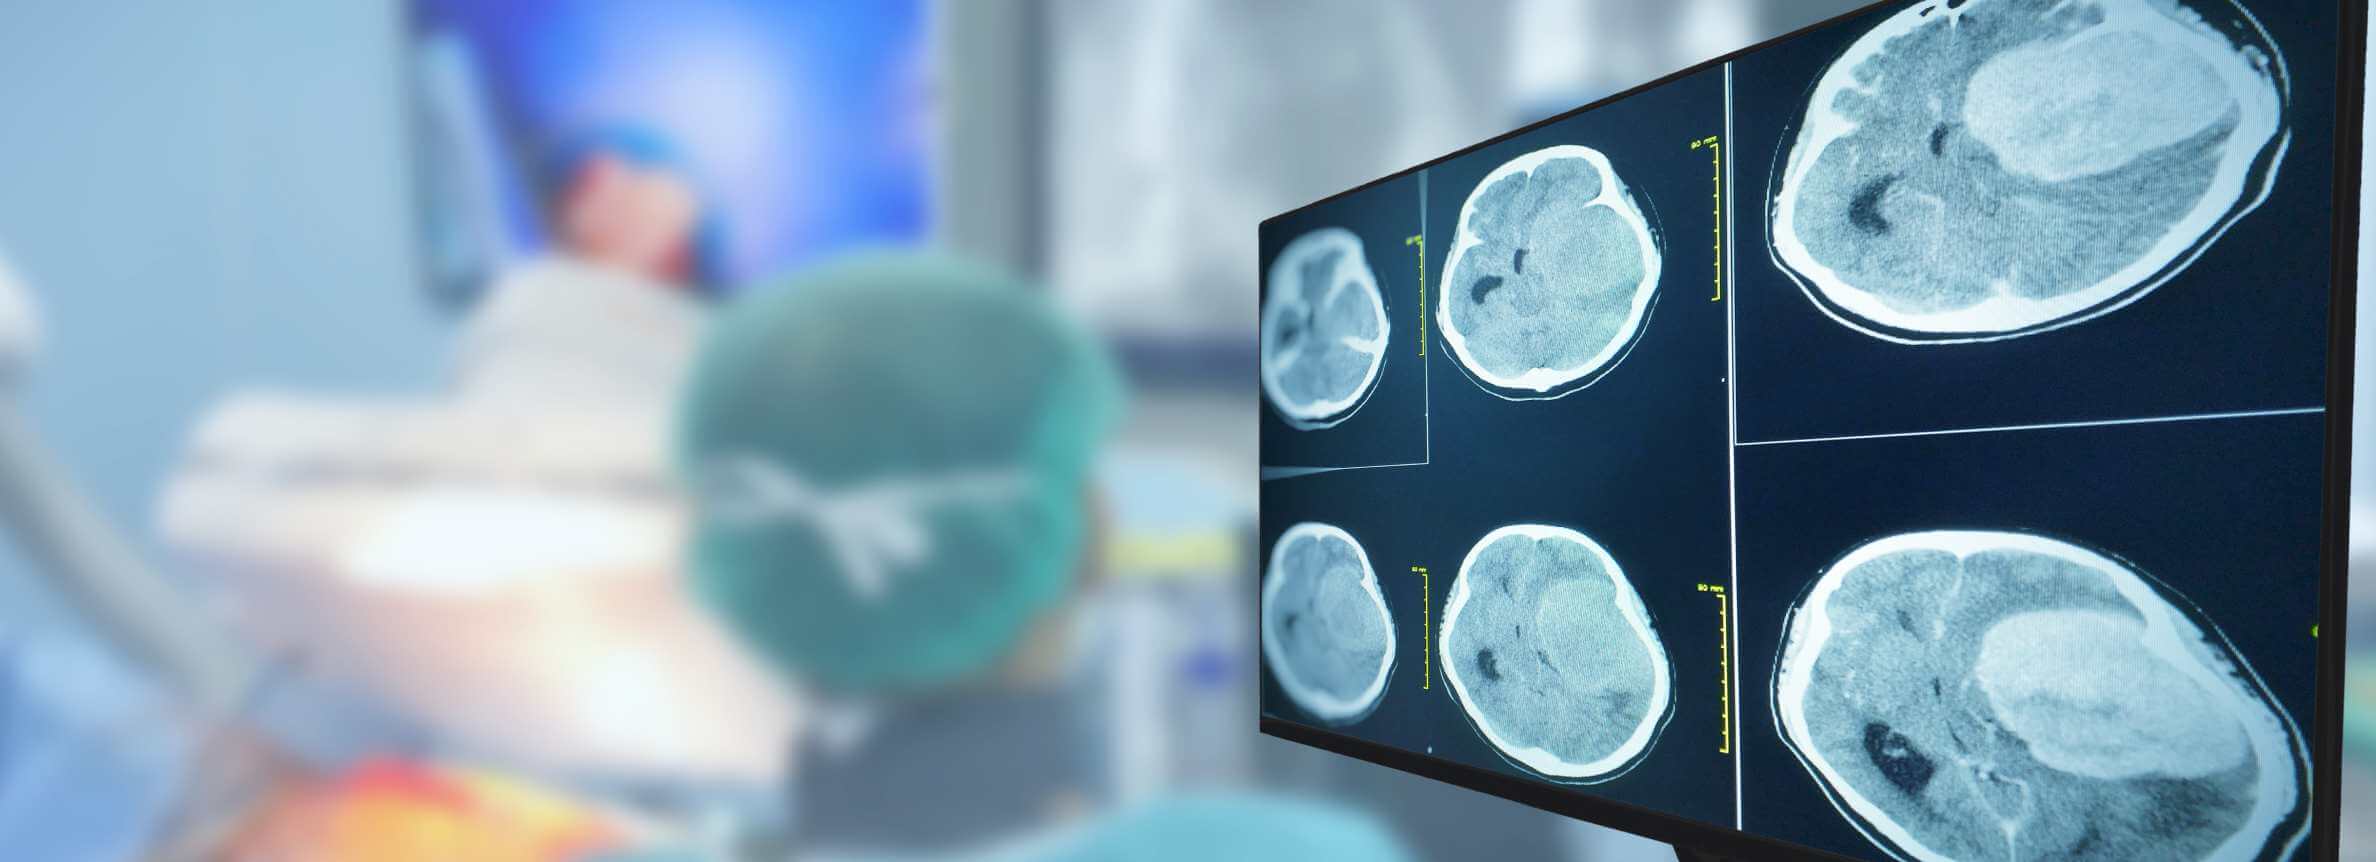

Prof. Gansauge's clinical experience in treatment with dendritic cells demonstrates its effectiveness with measurable results. His approach uses fresh, unfrozen dendritic cell vaccines. This maintains optimal cellular function and allows for targeting actual tumor antigens – distinguishing his method from clinics that freeze and store cells. Patients can see clear outcomes through MRI or CT scans. Scans may reveal shrinkage of glioblastoma cells, stabilization, or complete response to treatment.

During the entire course of treatment of glioblastoma, the patient remains under the supervision of a general practitioner, neurologist, and oncologist. In addition to clinical examinations, imaging diagnostics may be required – in this case, computed tomography (CT) is performed. This multidisciplinary follow-up model is about DC therapy for GBM in Germany, where treatment combines regular monitoring and a personalized approach to each patient.

One important element of the results is the control after the introduction of the dendritic cell vaccine. Glioblastoma in Germany is considered a diagnosis that requires particularly careful treatment control and regular medical monitoring (MRI or CT examinations that allow doctors to assess changes in tumor size and adjust the therapeutic strategy promptly).